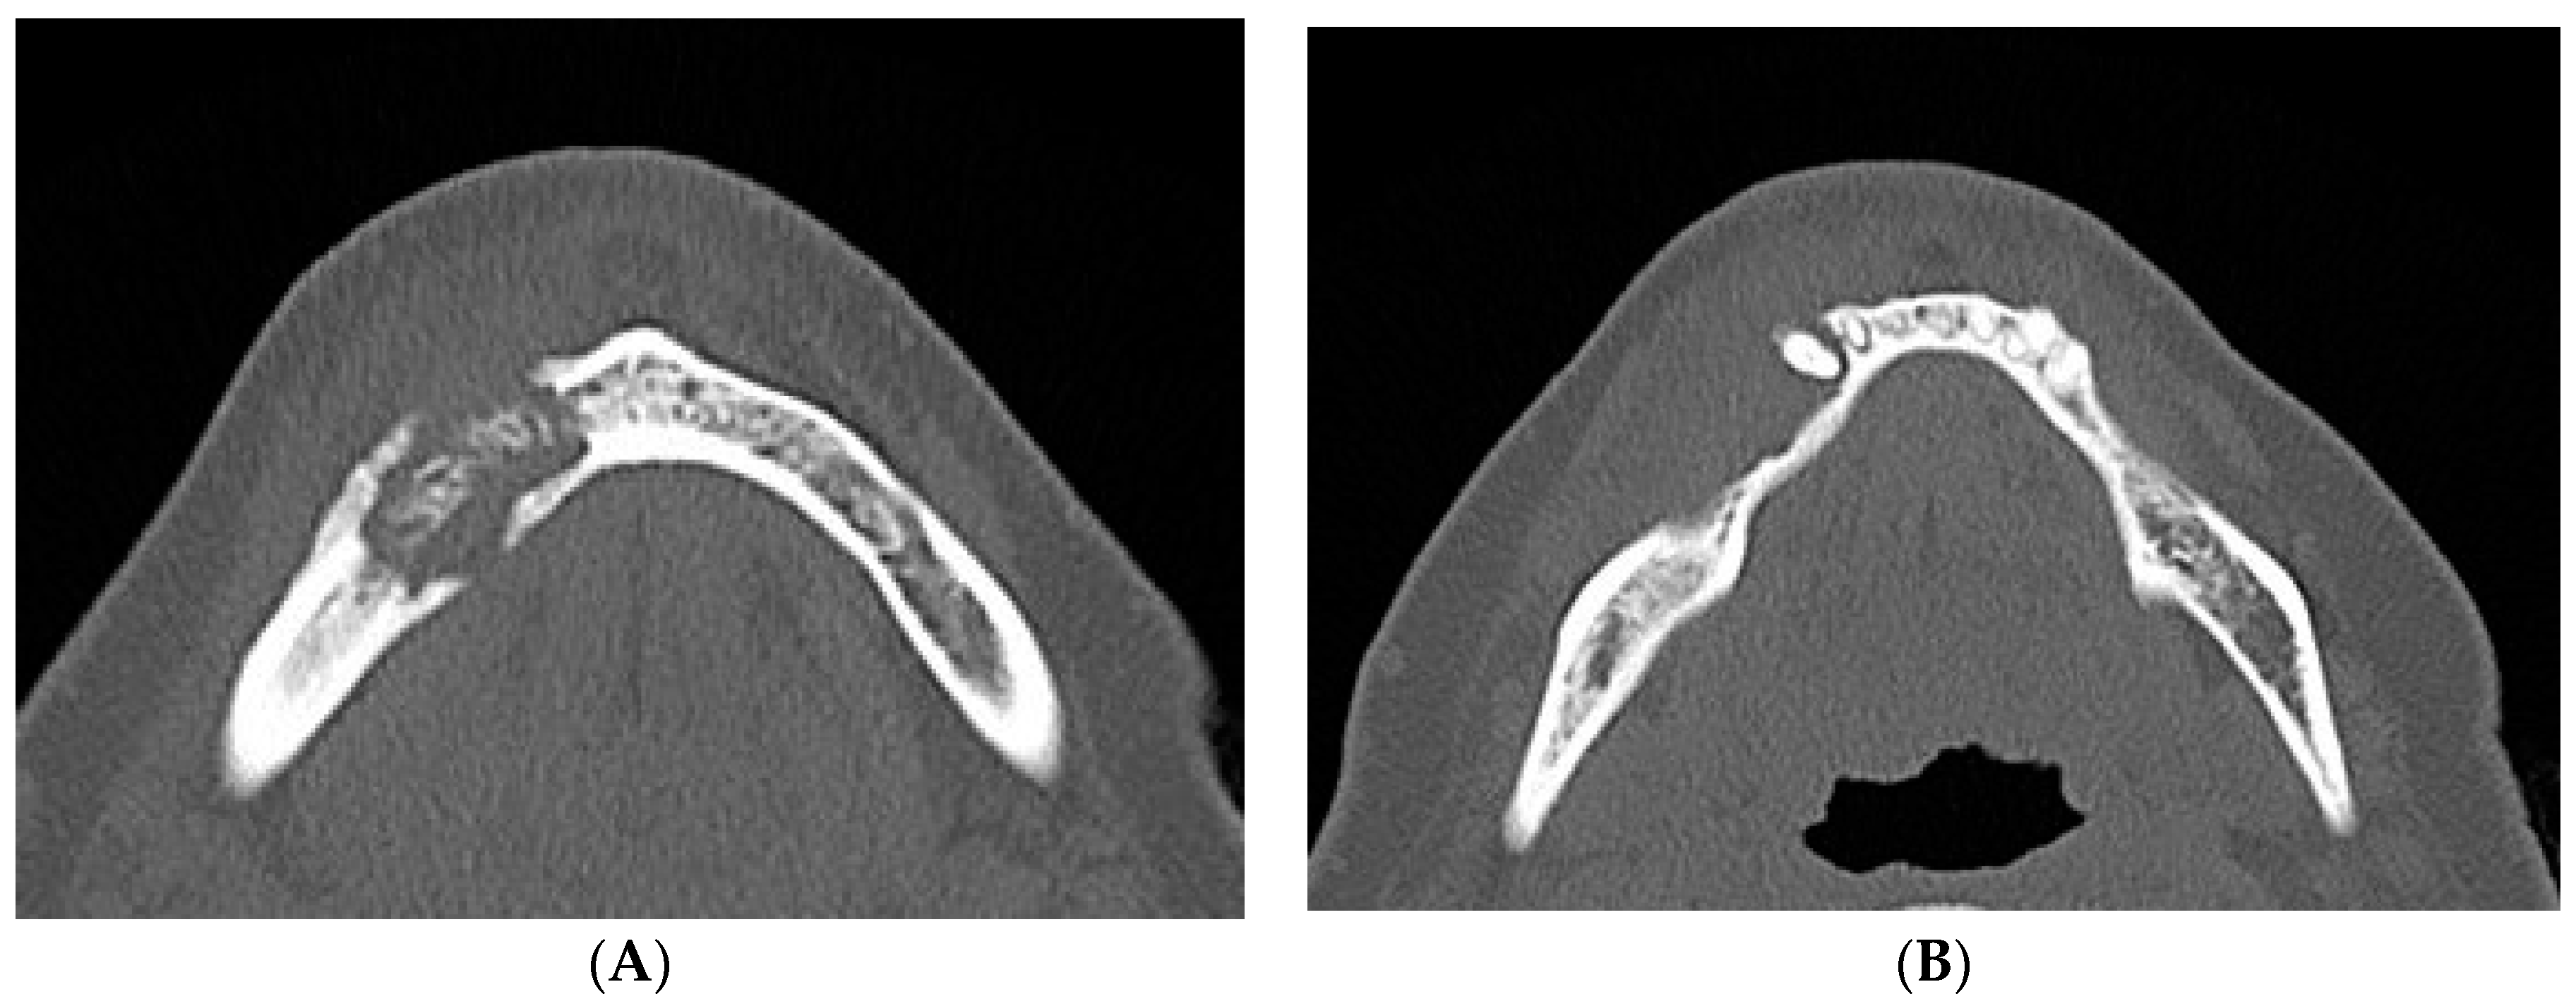

2. Case Report

- Bedogni, A.; Fedele, S.; Bedogni, G.; Scoletta, M.; Favia, G.; Colella, G.; Agrillo, A.; Bettini, G.; Di Fede, O.; Oteri, G.; et al. Staging of osteonecrosis of the jaw requires computed tomography for accurate definition of the extent of bony disease. Br. J. Oral Maxillofac. Surg. 2014, 52, 603–608. [Google Scholar] [CrossRef] [PubMed]